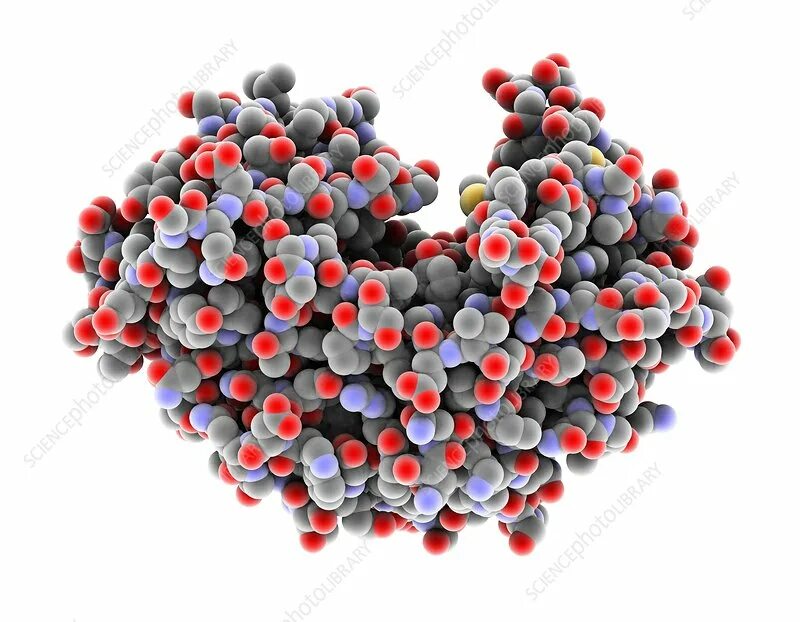

Структурная организация больших слюнных желез. Морфология секреторных отделов и системы выводных протоков. Печень: клеточные типы, характеристика классической печеночной дольки, портальной дольки и печеночного ацинуса. Кровоток и отток желчи. Морфология экзокринной части поджелудочной железы.

Механизмы переваривания и всасывания в ЖКТ. Переваривание углеводов, белков и жиров. Основные механизмы всасывания. Особенности всасывания веществ в различных отделах ЖКТ.